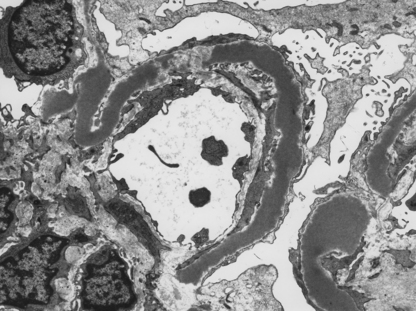

Membrano-proliferative glomerulonephritis

Membrano-proliferative glomerulonephritis (MPGN), a glomerular lesion with many causes, features both membrane thickening and proliferation (Fig. 21.8A). In addition, there is accentuation of the lobular architecture of the glomerulus. The thickened capillary walls, which have a duplicated ‘tram track’ appearance of the basement membrane revealed by silver staining (Fig. 21.8B), prompt the alternative name of mesangiocapillary glomerulonephritis (MCGN). This duplication is due to a new layer of basement membrane laid down by cell processes interposed between the endothelium and the basement membrane (Fig. 21.8C). Two main types are recognised.

image

Fig. 21.8 Membrano-proliferative glomerulonephritis. image The combination of mesangial cell proliferation and basement membrane thickening exaggerates the lobular architecture of the glomerulus. image MST stain shows the new layer of basement membrane giving rise to the reduplicated peripheral profiles characteristic of mesangiocapillary glomerulonephritis. image Electron microscopy shows the wall between the capillary lumen and urinary space to be thickened by the interposition of cellular processes and electron-dense deposits in relation to them.